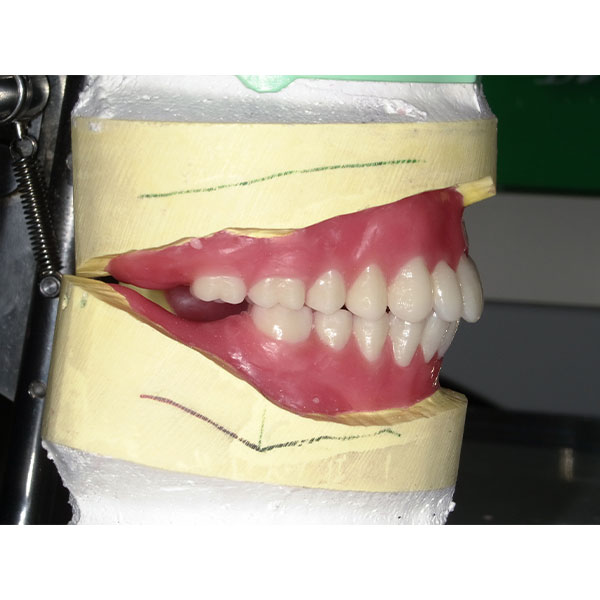

Après la mise en moufle et l'ébouillantage, les dents ont été repositionnées, conditionnées et des caractérisations blanchâtres, pourpres, orange clair, bleues et roses ont d'abord été réalisées au niveau du le bouclier labial. La base a ensuite été incrustée de résines pour prothèses de couleurs orange-rouge, rouge foncé, rouge clair, rose et rose foncé, et tous les polymères à chaud ont été pressés en une seule fois. Après le stockage sous pression, les prothèses finies ont été démouflées, finies et polies. La stratification anatomique tridimensionnelle de VITAPAN EXCELL en masse d'émail, de collet et de dentine avait un aspect absolument naturel dans l'anatomie muco-gingivale reproduite de la base prothétique. Le patient a pu s'habituer rapidement à sa nouvelle prothèse, notamment grâce à l'effet esthétique réussi. Après une courte phase d'adaptation et des corrections minimes dans l'environnement biodynamique, il s'est très bien débrouillé avec sa première restauration prothétique amovible complète et en était pleinement satisfait.